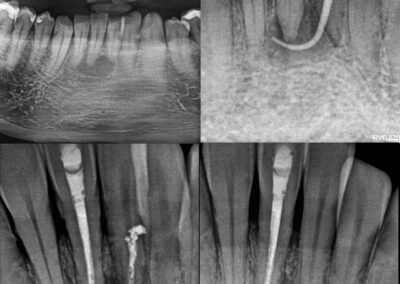

Poniżej prezentuję efekty leczenia kanałowego pod mikroskopem stomatologicznym. Wybrałam przypadki trudne i bardzo trudne. Do najbardziej czasochłonnych należy usuwanie z kanałów złamanych narzędzi i metalowych wkładów koronowo – korzeniowych oraz udrażnianie kanałów zobliterowanych.